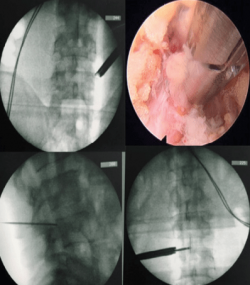

發稿日期:114年1月2日 隨著科技日新月異,各式微創手術層出不窮,讓人眼花繚亂,臺北市立聯合醫院中興院區骨科主治醫師陸逸民常碰到病患或家屬詢問:「醫師,這個手術可以微創嗎?」或是「我這個手術一定要微創嗎?」 陸逸民說,微創手術是現今醫療發展不可避免的趨勢,也是各家醫院及各科部互相較勁的兵家必爭之地。好處不僅是傷口較小且美觀,對周遭軟組織(包含肌肉、血管、神經等)的破壞也少,亦...... [閱讀更多]